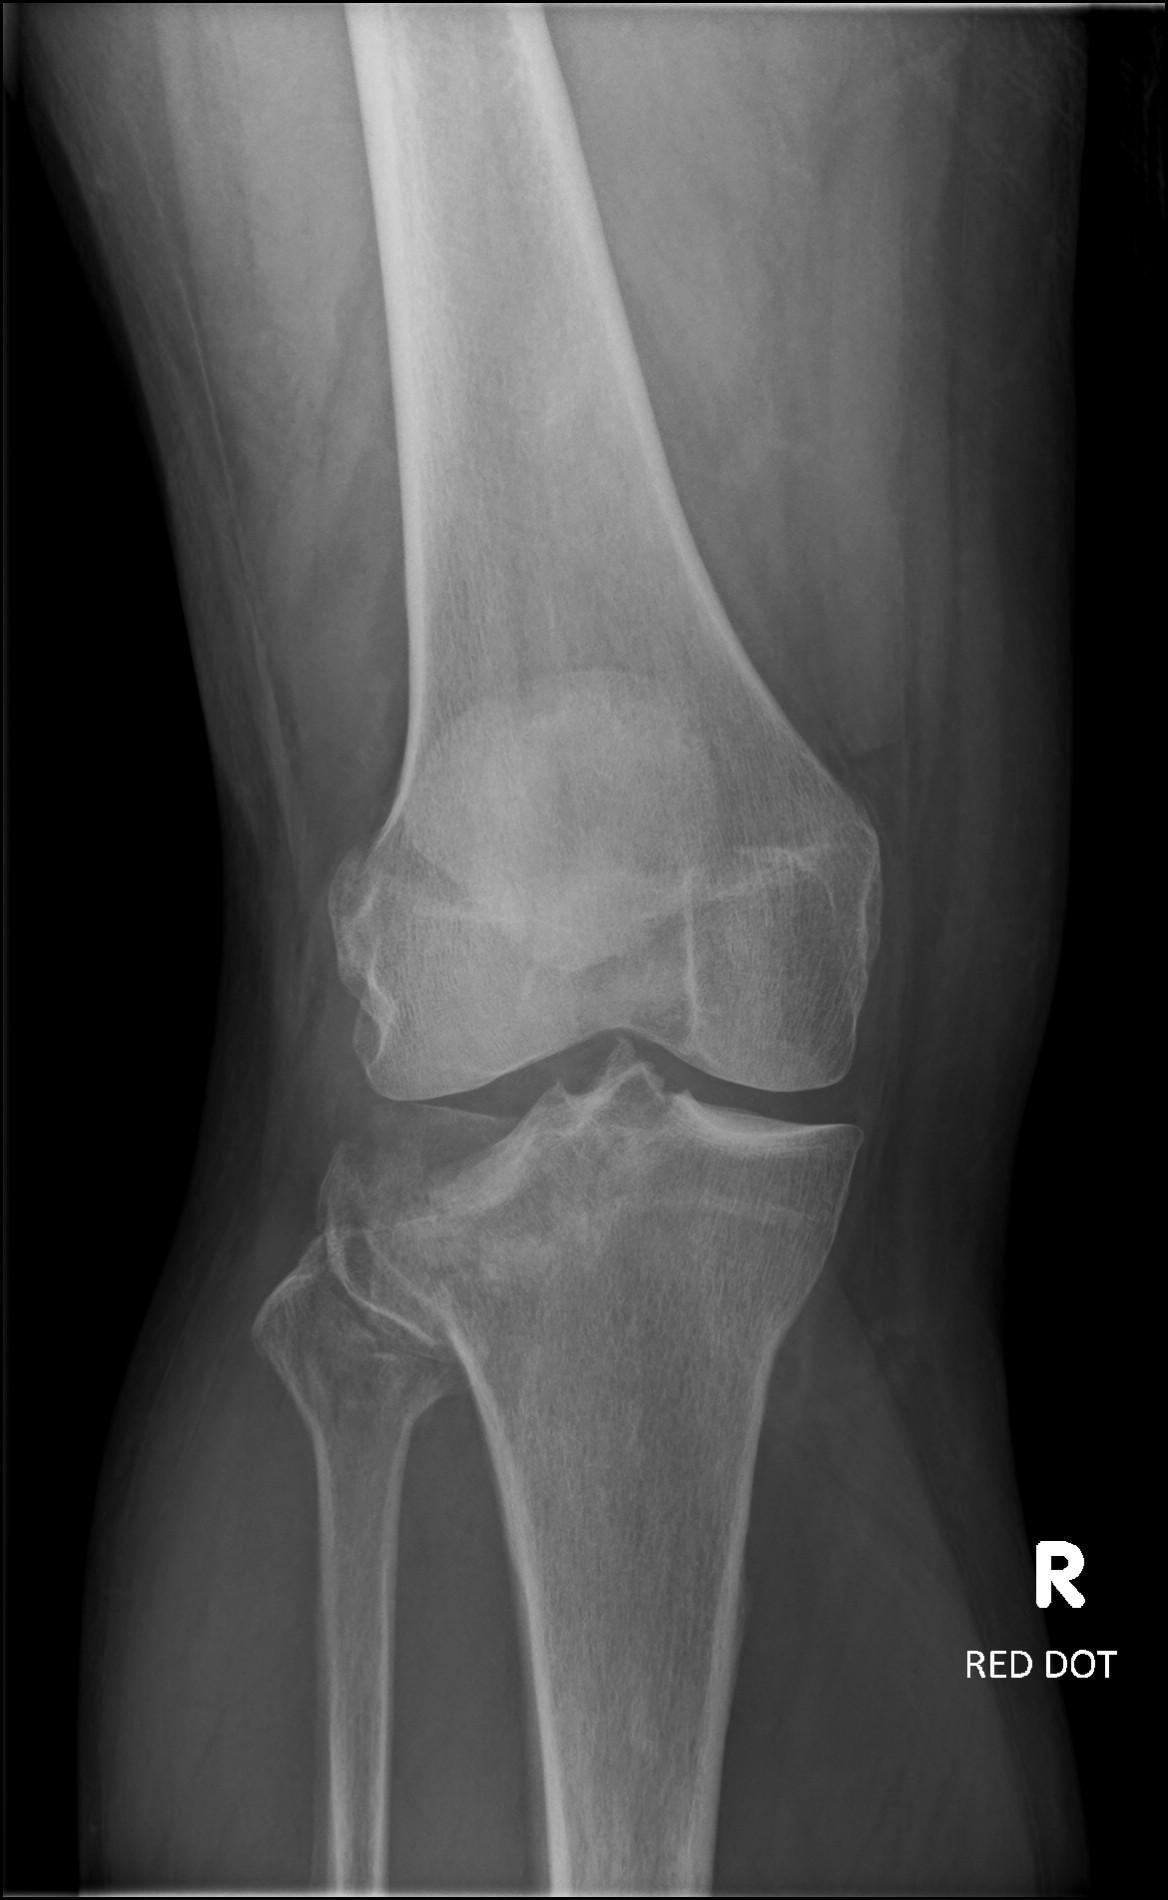

Fracture tibio-fibulaire

Ian Bickle, Radiopaedia.org. From the case rID: 76421

Avis chirurgical.